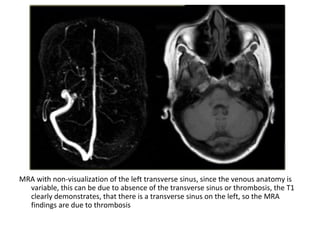

MRA with non-visualization of the left transverse sinus, since the venous anatomy is

variable, this can be due to absence of the transverse sinus or thrombosis, the T1

clearly demonstrates, that there is a transverse sinus on the left, so the MRA

findings are due to thrombosis

The same patient , CT shows the dense thrombosed transverse

sinus (yellow arrow) , the FLAIR shows the venous infarction

in the temporal lobe